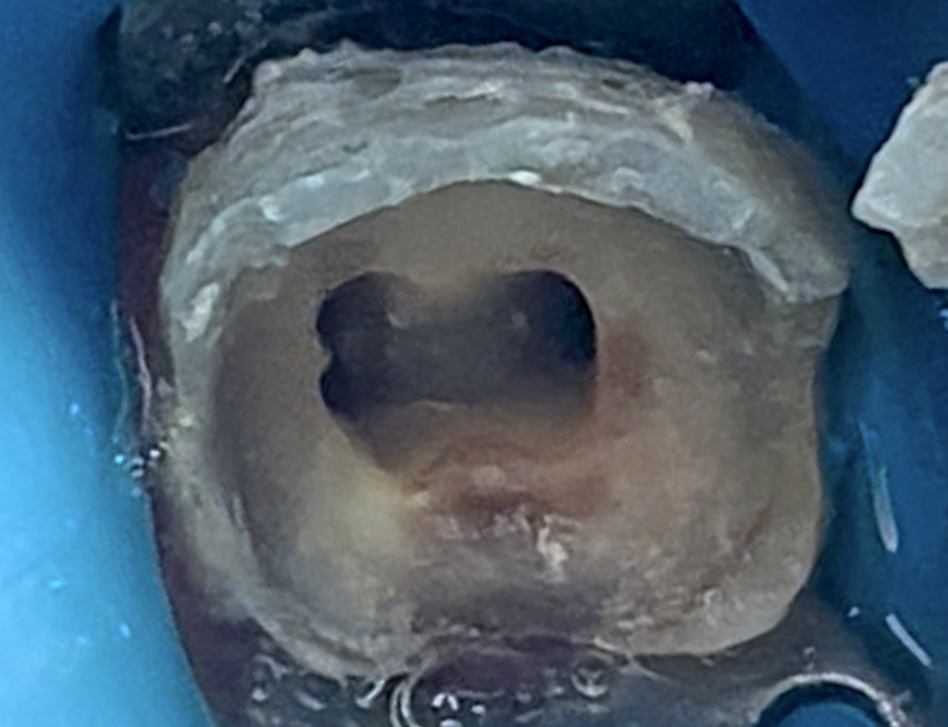

Access cavity after complete cleaning & shaping.

Now, trying clean cavity floor as much as possible to allow for maximum bond strength, God willing.